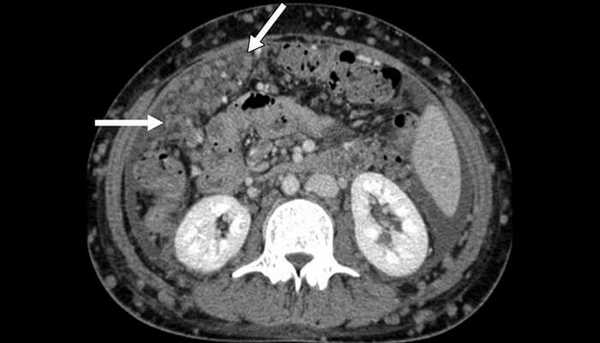

КТ при метастазе в тонкую кишку

Гематогенное метастазирование в тонкую кишку из очага первичного печеночно-клеточного рака у пациента 63 лет с анемией.

(а) При КТ в коронарной проекции в тонкой кишке визуализируется округлое гиперваскуляризованное полиповидное образование (стрелки). Отмечается кишечно-кишечная инвагинация, обусловленная метастатическим поражением тонкой кишки.

(б) Фотография макропрепарата: три полиповидных новообразования с центральным изъязвлением. Метастазы в тонкой кишке у мужчины 63 лет, которому год тому назад выполнена правосторонняя гемиколэктомия по поводу рака ободочной кишки.

Среди органов желудочно-кишечного тракта метастазы чаще всего встречаются в тонкой кишке. Первичные опухоли ободочной кишки, поджелудочной железы, желудка и яичников могут распространятся на тонкую кишку путем прямой инвазии или по брюшине. В тонкую кишку гематогенным путем могут метастазировать рак молочной железы, рак легких и меланома.

Метастазы в тонкой кишке могут приводить к непроходимости, перфорации, завороту и кишечному кровотечению. К типичным макроскопическим признакам можно отнести множественность поражения, доминирование экстрамурального компонента и подслизистое и субсерозное прорастание опухоли. При поражении тонкой кишки путем распространения по брюшине отмечается утолщение кишечной стенки, инфильтрация брыжеечной жировой клетчатки и патологическое утолщение большого сальника.

В случае гематогенного распространения метастатические опухоли представляют собой округлые или полиповидные образования с гладкой поверхностью, расположенные в области свободного края кишки. Гладкая или грибовидная интралюминальная опухоль с изъязвлением, как правило, определяется как «мишеневидное поражение». Визуализационные характеристики метастазов тонкой кишки могут не давать специфической информации о расположении первичной опухоли. Проведение КТ, МРТ или ПЭТ всего тела может быть информативным при поиске первичной опухоли.